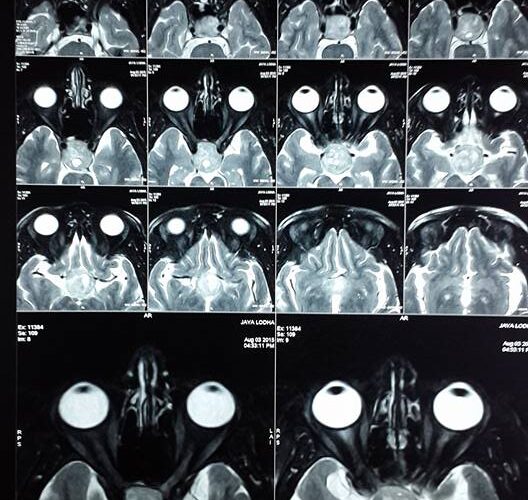

3 Endoscopic Pituitary Cases in Manik Hospital